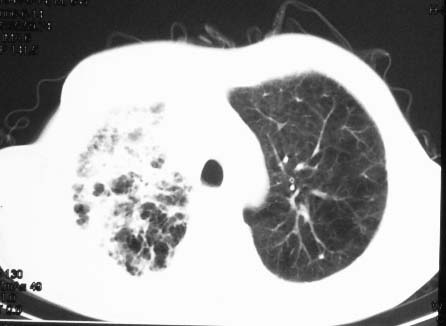

影象表现:右肺上叶大片状、网格状及索条致密影,蜂窝影,其内参杂斑点状小结节,密度不均匀,内见含气支气管像,纵隔内见肿大淋巴结.

抗感染病变无明显改善,右上叶大片状增弥不均匀病灶,夹杂网状及支气管充气像,肺门纵隔淋巴结肿大,右侧胸腔积液。考虑1混合感染伴肺间质改变[警惕特殊感染,如真菌]。2细支气管肺泡癌。建议结合临床及进一步检查[如痰,胸水脱落细胞检查及支气管镜检灌洗或穿刺活检

影象表现:右肺上叶大片状、网格状及索条致密影,蜂窝影,其内参杂斑点状小结节,密度不均匀,内见枯枝样含气支气管像,纵隔内见肿大淋巴结.胸膜广泛增厚,前胸壁似受累.少量胸腔积液.纵隔内淋巴结的直径>1.5cm.右侧胸廓体积缩小.考虑:1 肺结核合并间质纤维化 2 细支气管肺泡癌

右肺上叶大片状、网格状及索条致密影,蜂窝影,其内参杂斑点状小结节,密度不均匀,内见枯枝样含气支气管像,纵隔内见肿大淋巴结.胸膜广泛增厚,前胸壁受累增厚.少量胸腔积液.纵隔内淋巴结的直径>1.5cm.右侧胸廓体积缩小.考虑: 细支气管肺泡癌并肺内癌性淋巴管炎。